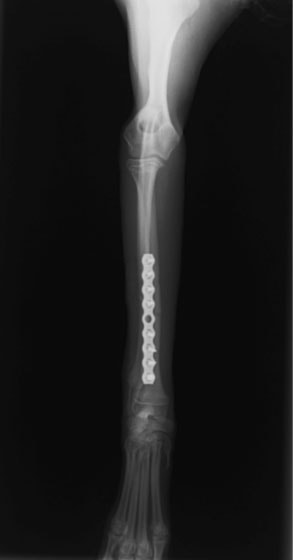

トイプードル 右遠位橈尺骨短斜骨折のALPSによる内固定

当院ではAdvanced Locking plate system(ALPS)と、Locking compression plate system(LCPS)という骨接合法で骨折症例の治療を行っています。

LCPは、スクリュー(ネジ)とプレート(金属の板)をロックする特殊な構造により骨折部位を固定する新しい世代のプレートシステムです。ひとつのホールでロッキングスクリューとスタンダードスクリューの使用を選択できるユニークな構造をしているため、骨折断端間の圧迫を目的とした従来型プレート固定法に加え、高い角度安定性を有するロッキングスクリューを用いた固定法の選択が可能です。従来のプレートシステムでは困難だった部分の骨折や癒合不全の症例に高い治療効果をもたらします。

1.骨膜上の血行障害は最小限

2.高い角度安定性

3.プレート設置時の整復位喪失の防止

4.スクリューのルースニング(ゆるみ)の防止

5.コンビネーションホール

6.粗鬆骨における固定性の向上

7.1.5mmと薄いプレートのため、超小型犬にも使用しやすい

8.抜去が不要となることが多い